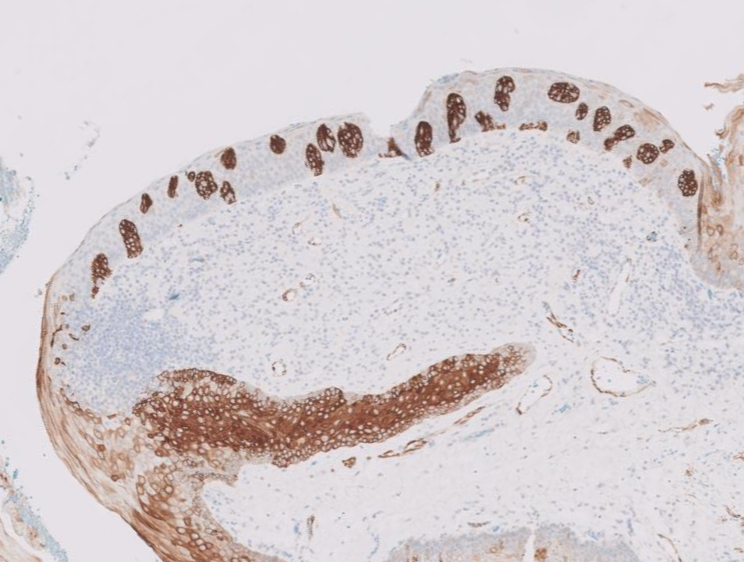

I'm so honored to receive the Dermatopathology Trainee World Cup 1st place for my presentation on cysts mimicking malignancies with Drs. Foulis and Gibbs! Had a great time, learned a lot, and met many amazing people @IntSocDermpath #ISDP2023 #PathTwitter #dermpath #dermtwitter